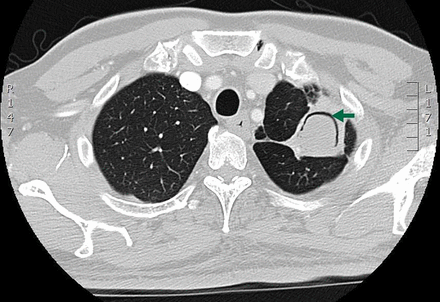

What is Invasive aspergillosis (IA)?

What are some primary investigations for ?Invasive Aspergillosis